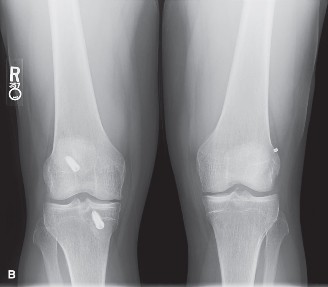

Understand rehabilitation of tendon to bone healing? CASE 4 A 54-year-old skier injures his right knee on the last run of the day. He describes getting his ski stuck in the snow and having an immediate onset of pain on the inside of his knee. He did not hear a pop and was able to make his way down the slope under his own power. Over the last few days, the pain has been worse when bearing weight. X-rays are shown in Figure 9–4A–C.

Figure 9–4 A–B

Figure 9–4 C